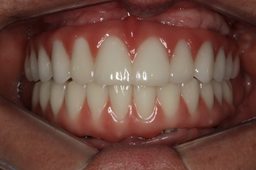

Após quatro meses, procedeu-se à cirurgia de reabertura e instalação dos pilares mini cônicos da linha de prótese do sistema CM e HI da Implacil De Bortoli e a paciente foi encaminhada para o protesista para instalação das próteses tipo protocolo. Nas figuras 9, 10 e 11 podemos observar o acompanhamento radiográfico e clínico após dois anos de follow-up.